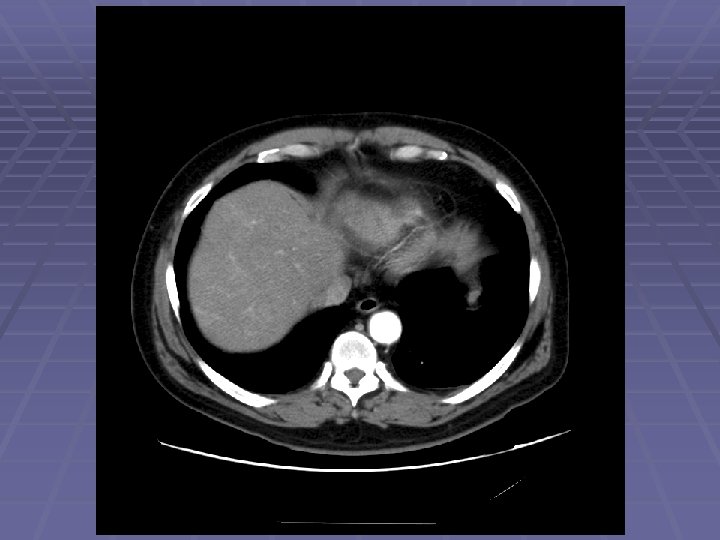

EUS Evaluation of Left Lobe of Liver